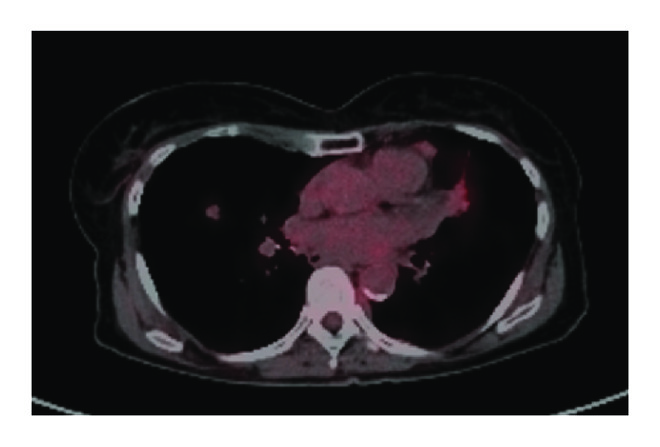

(a)

(b)

(c)

For the 108 patients included in this study, we found 195 instances of disease progression on ET that prompted a change in therapy. Progression was characterized as follows: diffuse progression, progression in greater than 3 sites; oligoprogression, progression in fewer than 3 sites with prior diffuse metastases (>6 sites of disease); and oligometastatic disease with progression, progression in 3 or fewer sites with prior limited metastases (<6 sites of disease). Examination of the patterns of failure revealed diffuse progression in 150 courses (77%), oligoprogression in 28 courses (14%), and oligometastases with progression in 18 courses (9%). On a per patient basis, most patients (69%) displayed only diffuse disease progression, with a smaller percentage of patients displaying oligoprogression (21%) or oligometastases with progression (10%) at least once in their disease course. Though these patients with oligoprogression or oligometastases with progression were similar in age and prior treatment to those patients who progressed diffusely, the patients who progressed diffusely were more likely to be Her2− (84% versus 74%, ), have more than 6 sites of disease at metastatic diagnosis (80% versus 56%, ), and have boney metastases (72% versus 47%, ) (Table 3). Additionally, though the median time to progression with each course of ET appeared similar between the two groups (Table 2), the overall survival of the patients that displayed diffuse progression was significantly shorter than the patients with oligoprogression or oligometastases with progression (median survival 3.1 years versus 6.5 years, ) (Figure 1(b)).

Of the 23 patients with oligoprogressive disease, 11 patients had only one site of progressive disease, 10 patients had two sites of progressive disease, and 2 patients had three sites of progressive disease. The most common sites of oligoprogression were bone (), liver (), locoregional (), and lung () (Figure 2). In addition, mixed locoregional and boney metastases were noted in two patients and one patient developed brain metastasis. Unfortunately, given the limited number patients in this study, no treatment or demographic factors were identified that were specifically associated with oligoprogression.